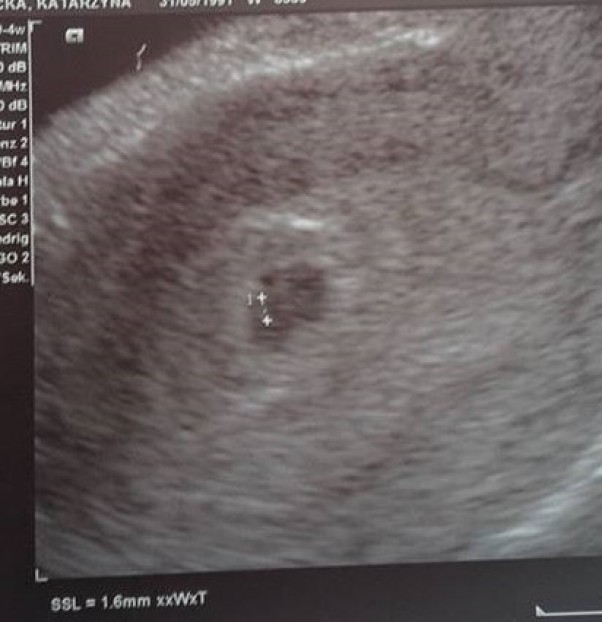

Nasza mała fasolka

w końcu się udało !! . Po rocznym staraniu w końcu z mężem zobaczyliśmy na usg naszą małą fasolkę :).. Wrażenie cudowne :)... Marzenia się spełniają a nasze małe ale zarazem wielkie szczęście ma 1,6 mm :)